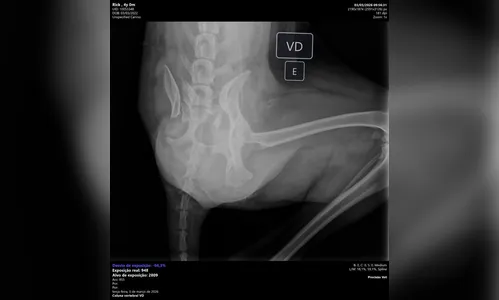

Exames realizados na clínica apontaram que o cachorro sofreu duas fraturas e está com dificuldades para se movimentar. De acordo com Angela, o animal sente dores, tem dificuldade para ficar em pé e até para fazer suas necessidades.

EXAMES:

Cão de três patas atropelado em Apucarana precisa de ajuda para cirurgia

AutorFoto: Lis Kato